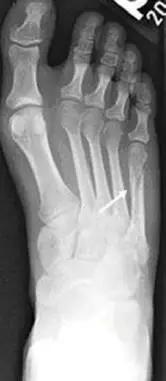

14.第五跖骨骨折

第五跖骨基底部骨折的不同类型:Stress 骨折;Jones 骨折:第五跖骨基底部以远 1 英寸内的骨折称为 Jones 骨折; Avulsion 骨折。

(来源:Radiopaedia)

Jones 骨折正位片(来源:Radiopaedia)

Jones 骨折斜位片(来源:Radiopaedia)

第五跖骨骨折还有 dancer’s fracture。

dancer’s fracture 正位片(来源:footEducation)

dancer’s fracture 侧位片(来源:footEducation)